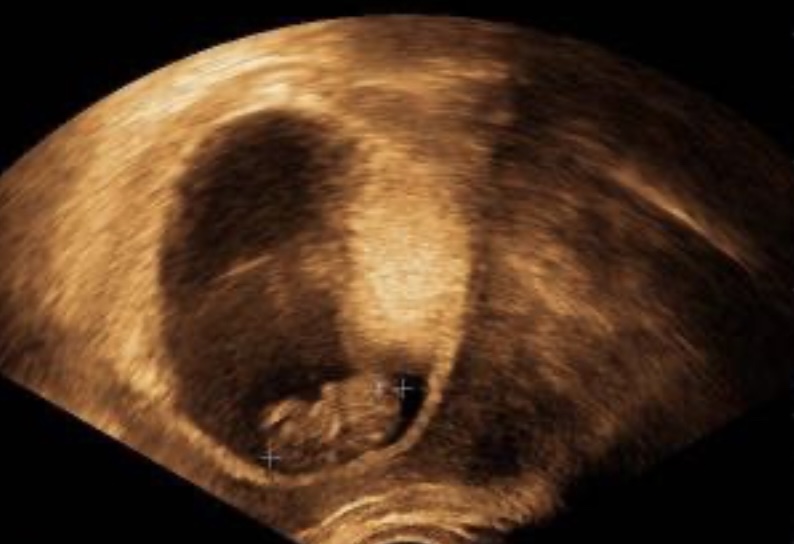

Ahoj. Tak včera jsem se dozvěděla, že jsem těhotná 9 tt. Ale mam dotaz. Tady mam krasnou fotecku ultrazvuku pry je miminko v pohode a tak. Ale dneska ścely den slabe krvacím a ja nevim co se deje? Mate nekdo zkusenosti? Prisla jsem tak o nekolik miminek ale tohle je poprve co se drzelo tak dlouho a vcera bylo vse v pohode a odedneska krvacím tak z toho mam teochu strach.